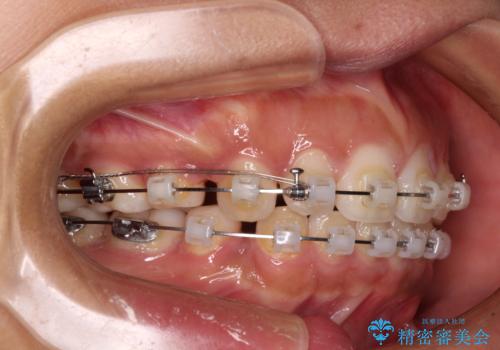

- クリアブラケット

- 2年6ヶ月

- 10-30回

口元の突出感を改善するため、上下左右第一小臼歯4本の抜歯を行い、ワイヤー装置による矯正治療を行うこととしました。